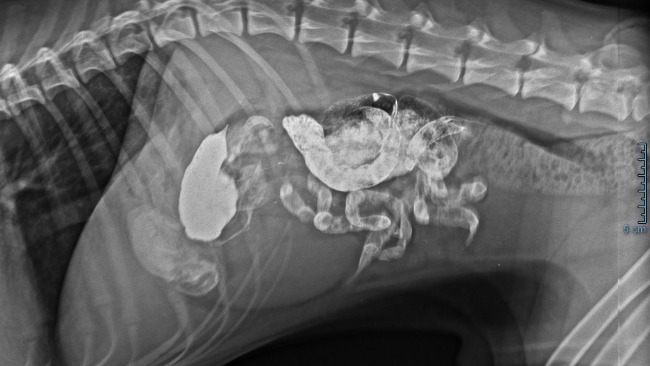

Znowu! Znowu coś się dzieje! Znowu jakaś choroba 😞 Oskarek poczuł się źle końcem grudnia. Jest w trakcie diagnostyki bo niewiadomo co się Mu dzieje a dzieje się uwierzcie mi z psiaka aktywnego, radosnego zrobił się psiakiem apatycznym, sennym nie chcę Mu się nic😞 Boli Go boli go brzuch boli go gęba, chudnie w oczach jest słaby 😭Lekarze obstawiają że to jelita. Dostał antybiotyk i serie zastrzyków, kroplówki.